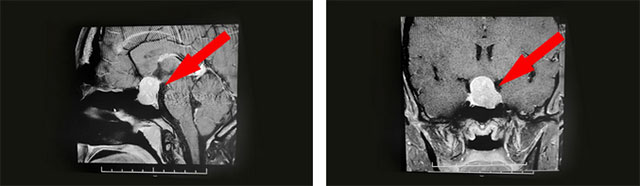

经过医院仔细检查发现:鞍区MRI平扫+增强显示:蝶鞍扩大,鞍底骨质下陷;鞍内垂体可见类椭圆形异常信号,大小约2.5*1.6cm,垂体柄未见明显显示;鞍上结构尚清,视交叉上抬;病灶与双侧海绵窦分界清晰;所示蝶窦局部黏膜增厚。

结合病史、影像等,神经外科6B病区潘仁龙主任、李士其教授、吴治群博士会诊后考虑为混合性泌乳-生长激素垂体大腺瘤,正是垂体瘤导致莉莉月经异常并停经,以及面容改变、肢端粗大等。手术指征明确,应尽快手术治疗。

▲ 影像检查显示:垂体大腺瘤,超蝶鞍生长